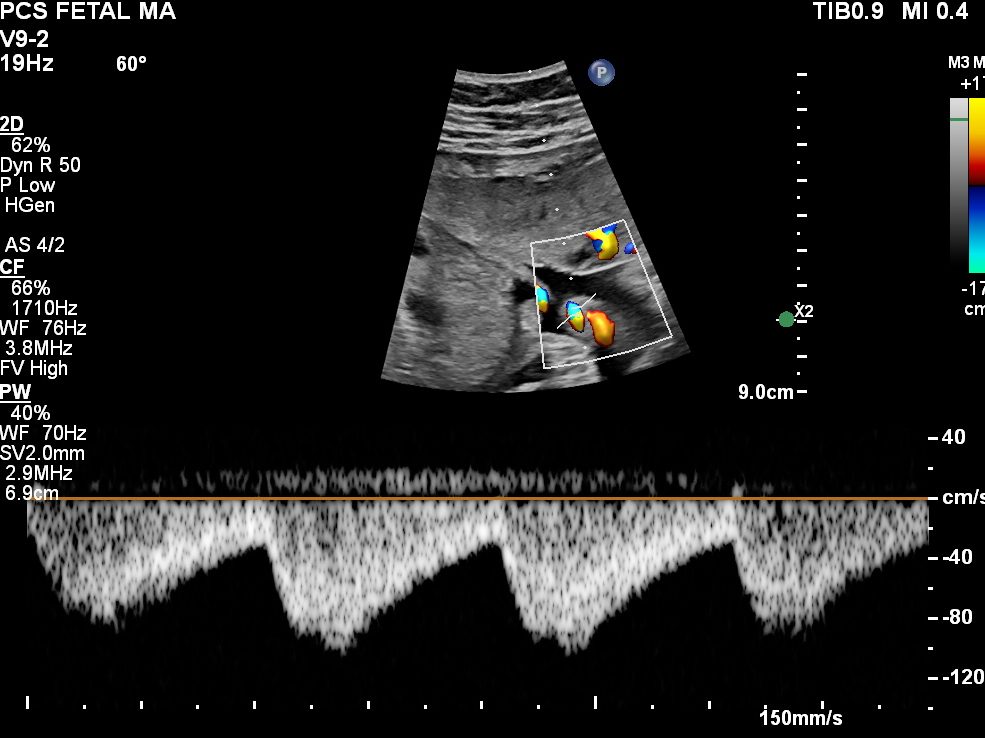

The Cerebro-Placental Ratio (CPR) is calculated by comparing the blood flow in the middle cerebral artery (MCA) to the umbilical artery (UA), giving clinicians a clear understanding of the fetus’s brain-sparing effect—the ability to redirect blood to vital organs like the brain when placental blood flow is insufficient.

It is calculated as the ratio between the pulsatility index (PI) of the middle cerebral artery (MCA) and the pulsatility index (PI) of the umbilical artery (UA).

CPR=PI-MCA/ PI-UA